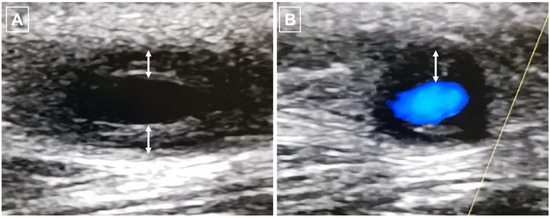

A Young Patient Presenting with Dilated Cardiomyopathy and Renal Infarction during Treatment with Isotretinoin: Mere Coincidence or Serious Side Effect of a Drug Commonly Used in Adolescence?

Isotretinoin or 13-cis-retinoic acid (RA) is one of the most effective and widely used drugs for the treatment of severe acne vulgaris. Despite being deemed safe, no definite consensus has been reached on the cardiovascular risk of RA derivatives. We report a case [...] Read more.

Isotretinoin or 13-cis-retinoic acid (RA) is one of the most effective and widely used drugs for the treatment of severe acne vulgaris. Despite being deemed safe, no definite consensus has been reached on the cardiovascular risk of RA derivatives. We report a case of heart failure due to dilated cardiomyopathy (DCM) and concomitant renal infarction occurring after 5 months of isotretinoin use in a previously healthy 18-year-old male. The patient, with a history of acne vulgaris, presented to our emergency department with left iliac fossa pain and effort dyspnea. A trans-thoracic echocardiogram showed DCM and severely reduced left ventricle ejection fraction (LVEF: 29%). During hospitalization, a total body computed tomography (CT) showed an ischemic lesion in the left kidney. Ischemic, autoimmune, infective, and heritable causes of DCM were ruled out. Cardiac magnetic resonance (CMR) evidenced LV circumferential mid-wall late gadolinium enhancement. Heart failure therapy was promptly started and up-titrated, but only poor LVEF improvement was detected overtime. Our case aims to raise awareness on rare life-threatening cardiovascular events possibly associated with isotretinoin use. To the best of our knowledge, this is the first described case of renal thromboembolism and severe DCM leading to implantable cardioverter-defibrillator (ICD) implantation occurring during isotretinoin treatment. Full article